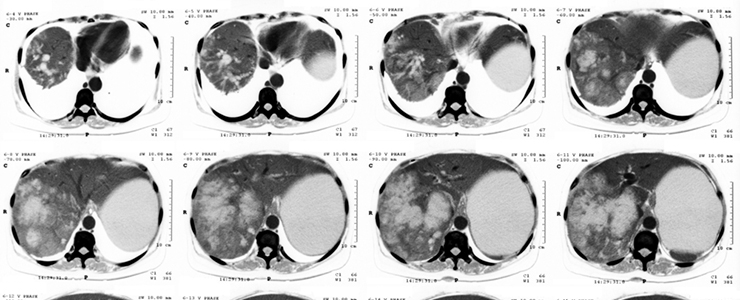

肝臓がんは他の臓器に転移しやすく、さらにはどこに転移するかも予測できないため、治療には早期発見、早期治療開始が重要なポイントです。

人間ドックでは他にも肝臓病の発見にかかわる検査を実施します。血液検査や便検査もたいへん重要なのですが、これらは肝臓のどこに病変が起きているのか、どの程度の大きさの病変があるのかを調べるような内容ではありません。そこで、肝機能の低下が認められた方、また、肝機能の低下を予測している方、予防したい方については、超音波検査やCT検査、MRI検査などを併せて受診するといいでしょう。いずれも人間ドックでは人気がある項目で、肝臓病の早期発見に大変有効です。

特に「CT検査」は立体的に病変の位置を特定できる検査なので、単独で受診するよりも比較的費用を抑えられる人間ドックで、効果的な他の検査項目と組み合わせて受診することをおすすめします。